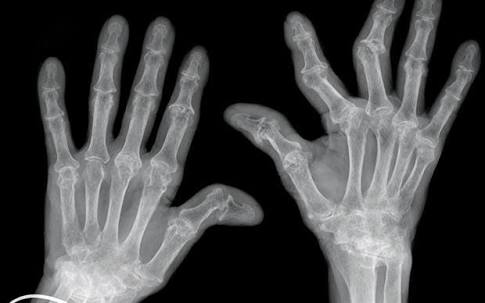

类风湿关节炎,其主要的病理基础是滑膜的改变,当滑膜出现了类风湿滑膜炎改变以后,会逐渐的破坏掉关节腔内的软骨,导致关节间隙的狭窄和关节的粘连,严重的影响患者的生活质量,很多人因为手部的变形甚至筷子都拿不了。

类风湿性关节炎的患者早期通常会表现出明显的晨僵,尤其是表现在手部。很多患者会在早期的时候表现出早上起来的时候,手指的僵硬感,握不拢,而且握拳的时候会有疼痛,通常需要经过30分钟左右的时间才能缓解。

如果患者出现了以上的情况,那么建议您一定要到医院做一个采取的化验,我们叫风湿4项,不仅可以明确是否有风湿和类风湿,还可以对血尿酸进行检查。为了更加准确的判断病情,我们同时建议检查抗环瓜氨酸抗体。如果这两项都表现为阳性,那么患者患有类风湿关节炎的几率是特别高的,可以达到80%。

当然当很多患者已经到了晚期,关节已经出现了明显的变形,从相关的查体以及x光片子,也可以明确患者是否存在类风湿性的关节炎。从下图您仔细看就会看出正常的手与类风湿性关节炎手部的骨骼改变。

另外类风湿这种疾病也会导致患者出现比较严重的骨质疏松,建议类风湿患者一定要做双能x线检查,明确自己是否存在骨质疏松,或者说骨质疏松到了什么样的程度,根据结果进行系统的抗骨质疏松治疗。